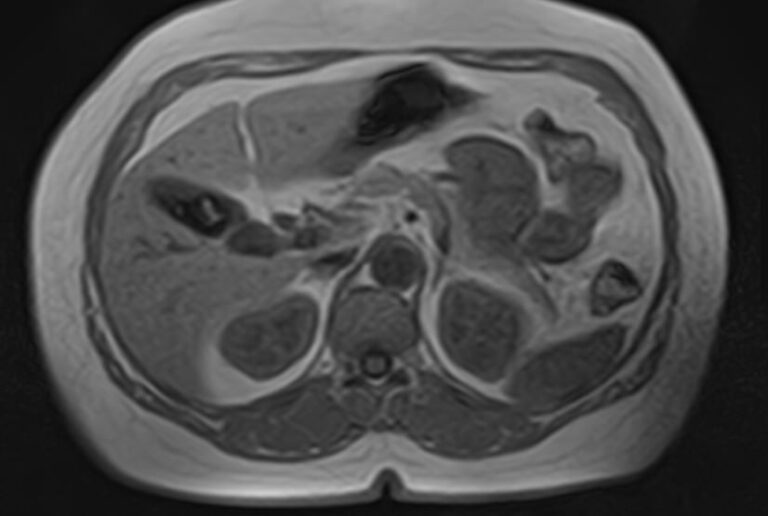

Современным методом обследования для диагностики заболеваний поджелудочной железы является магнитно-резонансная томография. В клинике «Доступная медицина» МРТ поджелудочной железы проводится на новейшем высокопольном томографе экспертного уровня TOSHIBA VANTAGE TITAN 1,5 Тесла, который позволяет получать послойные изображения исследуемой зоны с высокой степенью разрешения. Для лучшей визуализации и выявления минимальных изменений в органе применяется контрастное усиление путем внутривенного введения гадолиниевого контрастного препарата (Магневист, Гадовист, Омнискан и др).

С помощью компьютерного моделирования аппарат создает объемные изображения превосходного качества. Возможности аппарата позволяют поставить точный и достоверный диагноз, что дает возможность выявлять заболевания на ранних стадиях и назначать своевременное лечение.

В процессе МРТ поджелудочной железы получают серию снимков органа, по которым можно оценить следующие параметры:

МР-томография выступает уточняющим методом диагностики при сомнительных результатах УЗИ. Процедура позволяет определить характер, локализацию и масштабы патологического процесса.

Метод применяют при подозрении на онкологический процесс для первичной дифференциации доброкачественных и злокачественных опухолей. Подробные сведения об анатомии поджелудочной железы позволяют исключить осложнения панкреатита. МРТ также применяется для подготовки к хирургическим операциям и контроля результативности лечения.